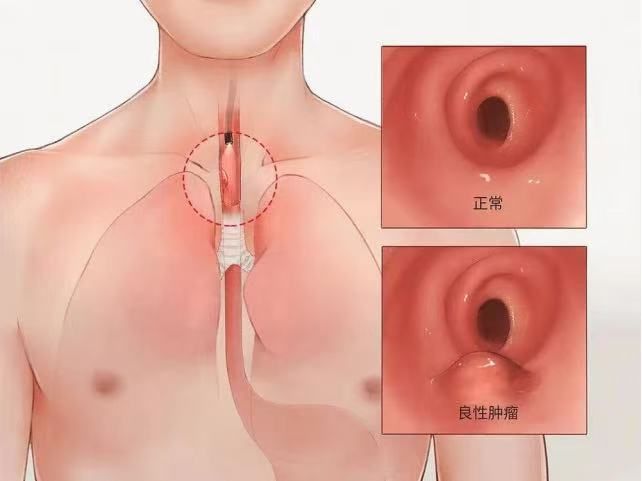

食管平滑肌瘤是食管肿瘤中常见的良性疾病,食管粘膜下肿瘤因症状较轻或无症状,常被忽视。一般表现为轻微吞咽不适、梗阻感或胸骨后不适,伴有上腹部不适、反酸、嗳气及食欲不振等,这些都跟食道部位的肿瘤有最为直接的关系,还会出现咳嗽、呼吸困难、哮喘等,主要的原因就是肿瘤太大了把气管压迫了。症状多呈间歇性发作,因为这样的一个肿瘤发展进程非常的慢,吞咽困难呈现间歇性,有时候严重一些,有时候又正常了。食管平滑肌瘤虽为良性疾病,但进一步发展后,不仅会影响生活,还会压迫周围脏器产生一系列并发症。一旦诊断明确,建议及早进行手术治疗。西安交通大学第二附属医院胸外科姜建涛主任作为国内知名专家,熟练掌握胸外科常见病、疑难病的诊治,敢于挑战高难度手术,为患者的长期生存和更优的生活质量带来了福音。